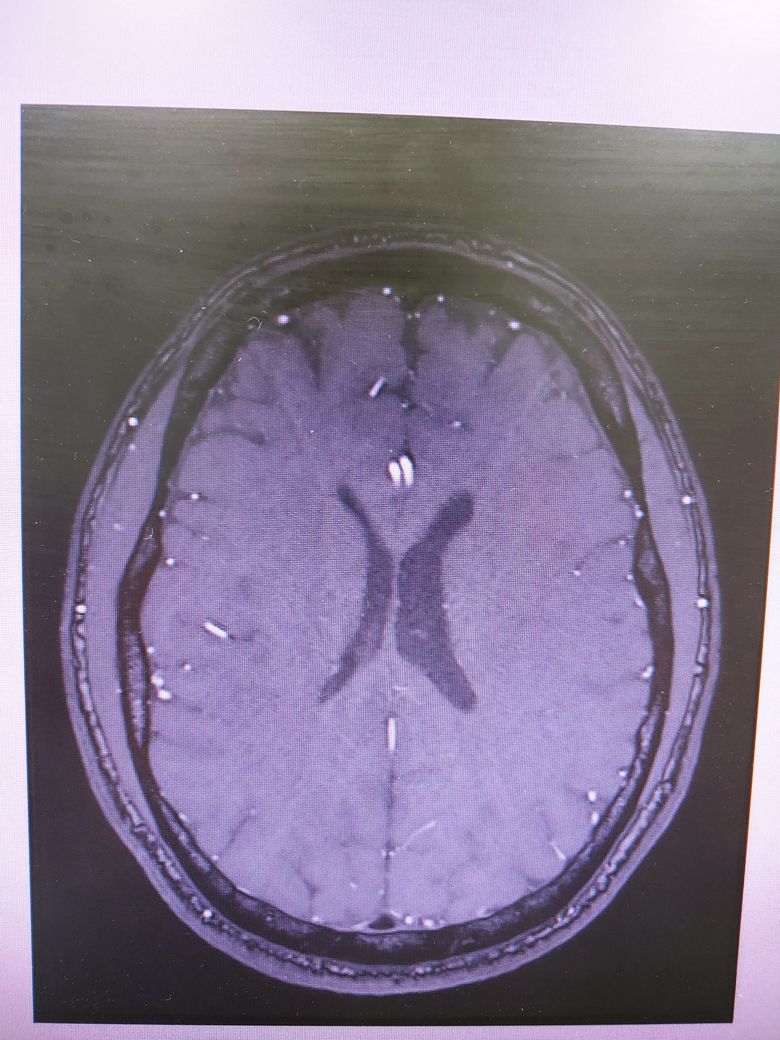

• 2번 째 사진

4컷만으로는 MRI에 대한 충분한 판독이 어렵지만 큰 이상은 없는것으로 보입니다.

특이 이상소견은 보이지 않으나 mri의 경우 4장으로 판단하는 것이 아닌 각 단면마다의 연속적인 영상을 보아야 알수 있습니다. 그리고 각 setting마다 볼수 있는 것도 다르며 보다 명확한 평가를 위해서 담당 선생님께 보다 구체적인 설명을 들으시길 바라며 최근 멍한 증상이 심해졌다면 뇌파 검사 등이 요구될수 있습니다. 우선적으로 기존에 다니셨던 병원을 내원해 진료를 보시고 추가적으로 신경과 내원 또한 고려해볼 수 있습니다. 감사합니다.

올려주신 사진 상에서는 이상소견이 확인되지 않습니다.

MRI의 경우 이렇게 몇컷만 보는것이 아니고 전체를 확인해야하기 때문에 다른 신경과 전문의 진료를 받아보시고 MRI 판독을 요청해보시는게 좋겠습니다.

뇌MRI는 단순히 4장 가지고 판독할 수 없습니다.

걱정이 되신다면, 영상의학과 전문의 중에서 뇌MRI를 전문으로 보는 의사에게 판독받는 것이 가장 정확할 것입니다.